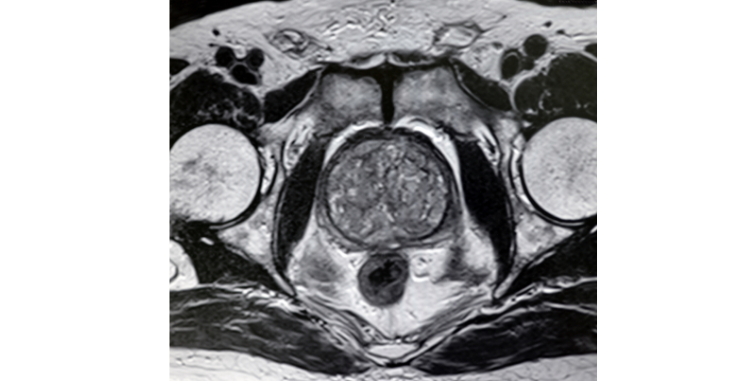

骨盤MRI(前立腺・婦人科)

所要時間約25分 料金:22,000円(税込)

男性の方

健診において血液検査にてPSA(前立腺の腫瘍マーカー)を選択される方が多いですが、MRIによって撮像(さつぞう)した骨盤内を詳細に検査することにより前立腺の大きさや膀胱の様子まで調べることができます。

女性の方

子宮頸がん検査は精度の高い検査ですが、更年期には子宮体部にも異常がでやすくなります(下図参照)。女性の骨盤MRI検査ではエコーより鮮明に子宮全体を検査することが出来、がんのみでなく他の病気や膀胱までを検査することが出来ます。服を着たまま検査をするため、婦人科に抵抗がある方にもおすすめの検査です。